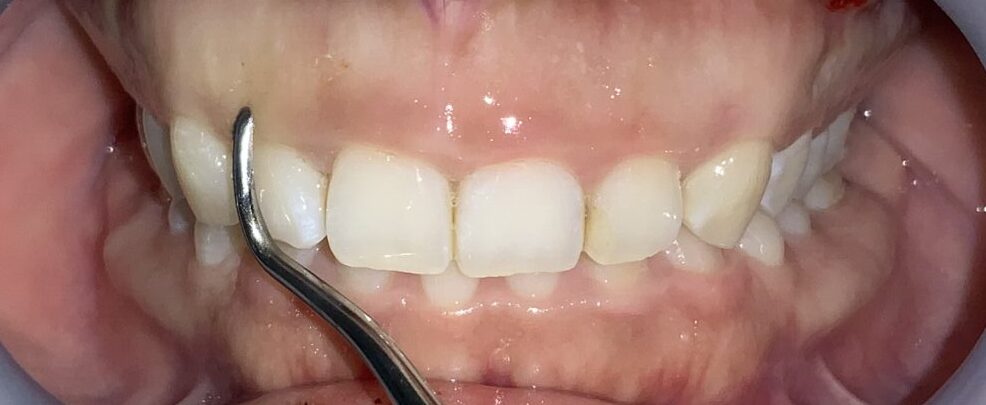

患者様のOKが出たので、すべての歯の治療を行いました。

歯ぐきの面積が少なくなって、笑った時の歯ぐきが見えなくなり、歯の形も、歯ぐきの形も綺麗に改善しました。

歯ぐきが一部黒ずんでいる部分は、数日で改善するのでご安心ください。